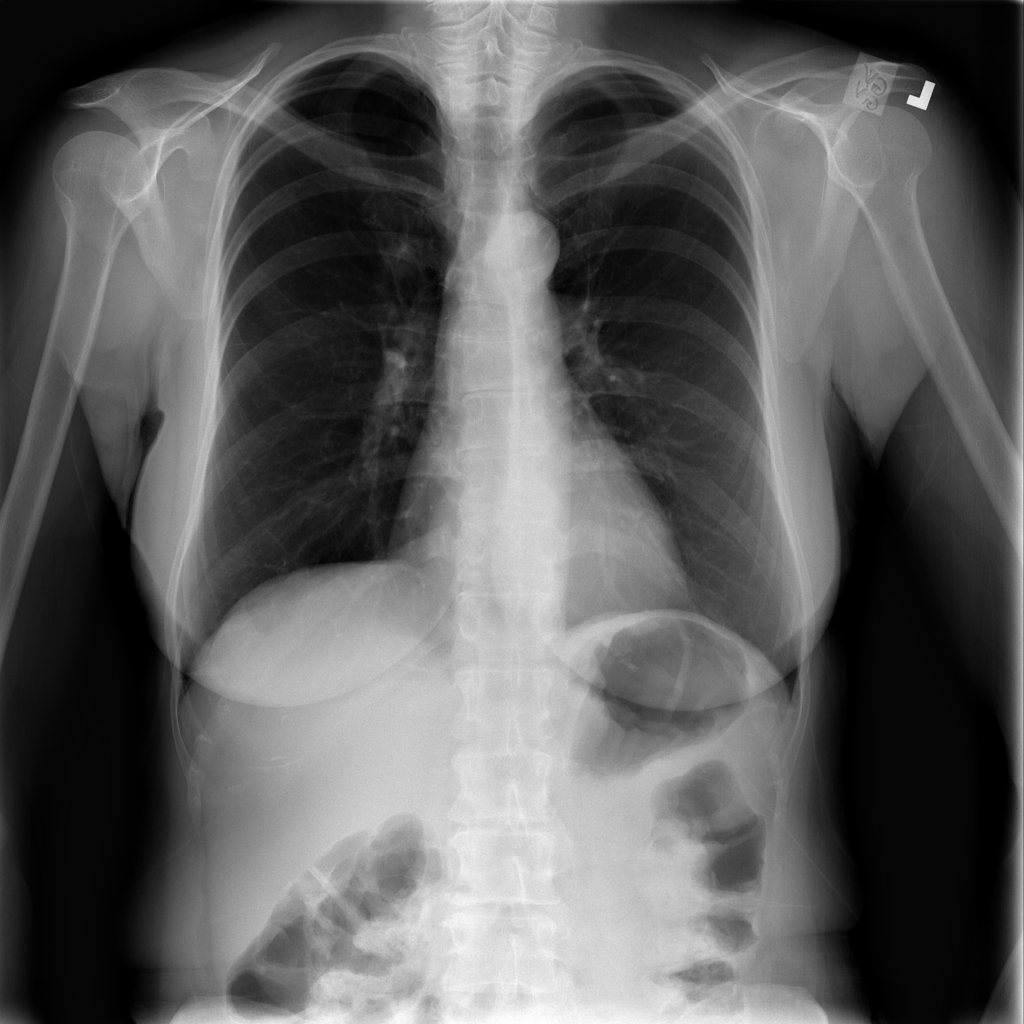

Nodule

A nodule is a small rounded opacity in the lung or chest field. It is a descriptive imaging finding that can be benign or more concerning depending on size, appearance, and context.

Showing up to 90 reference images for Nodule.

PAT-250B · IMG-000Nodule

PAT-250B · IMG-000

PA